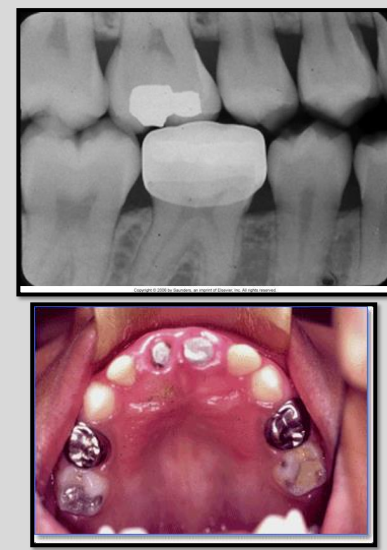

Describe the appearance of Porcelain-fused-to-metal crown on a radiograph.

The metal component appears completely radiopaque

Porcelain components appears slightly radiopaque.